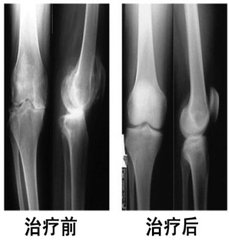

• [骨质增生] 膝盖骨质增生

导读: 膝盖骨质增生临床表现:初期,起病缓慢者膝关节疼痛不严重,有可持续性隐痛,气温降低时疼痛加重,与气候变化有关,晨起后开始活动,长时间行走,剧烈运动或久坐起立开始走时,膝关节疼痛僵硬,稍活动后好转,上、下